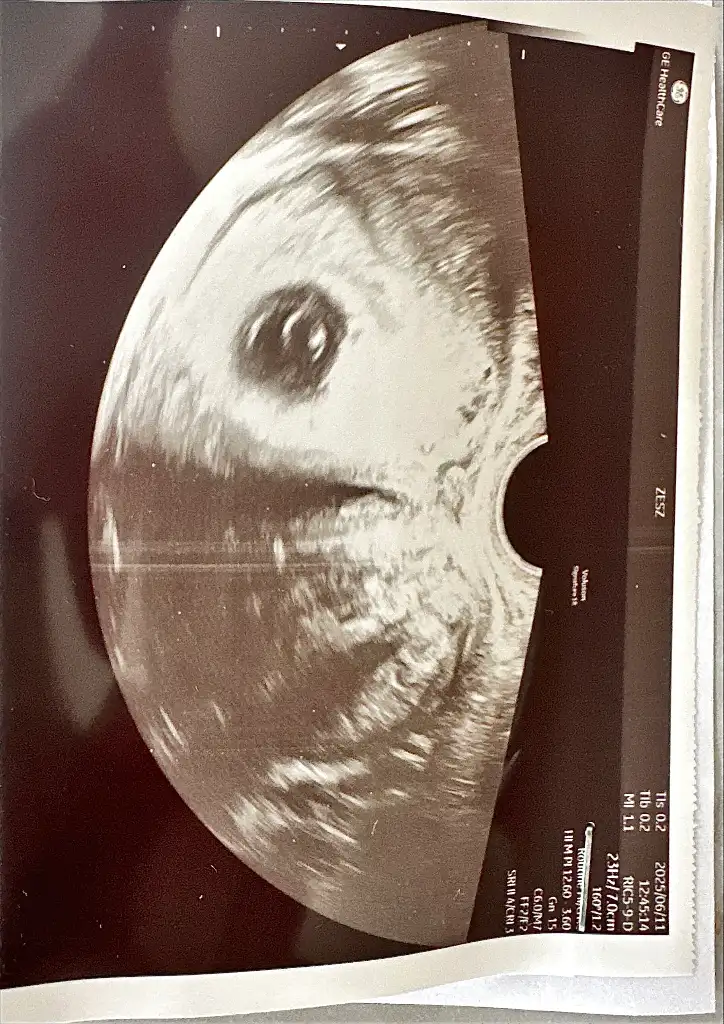

Dun usg boyle gozuktu. Benzer bir gorsel goren arkadaslar yorumlayabilir mi?

Eklentiler

• IMG_4681.webp

IMG_4681.webp

96,5 KB · Görüntüleme: 32